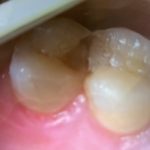

きれいに治った写真は次のブログでアップしますね🙌🙌💛💛💛💛🧡🧡🧡🧡🧡

早めに治療すればすぐに終わりますよ💓💓